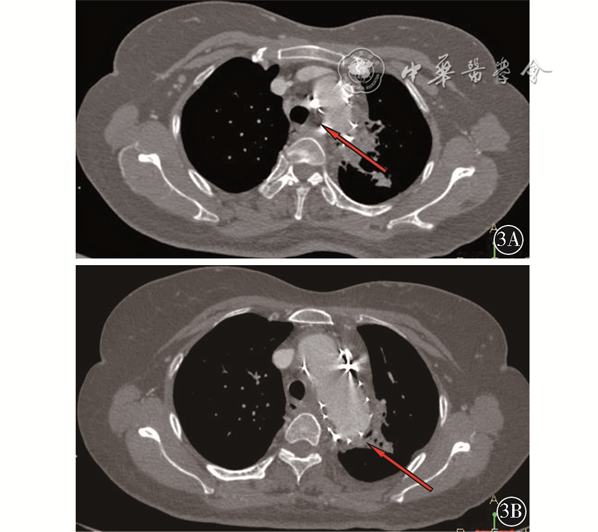

患者 女性,52岁。因“呕血1 d”于2020年9月21日入院。2017年11月6日因胸主动脉瘤行TEVAR(32-200 mm,美国Medtronic公司)、左颈总动脉重建术(Viabahn,8-50 mm,美国Gore公司)。既往白塞病2年未规范化治疗,高血压病10年,自述血压控制尚可,脑梗死病史时间不详,自述近6个月有“咯血”病史。体格检查:一般状态欠佳,生命体征尚平稳,急性病容,口唇苍白。辅助检查:白细胞:17.05×109/L,中性粒细胞百分比89.80%,红细胞:2.42×109/L,血红蛋白:59.00 g/L。给予抗炎、补液、抑酸、止血、输血等支持、对症治疗。电子胃镜:食管距门齿25 cm见黏膜深度凹陷,表面结节样隆起,底窥视不清,似有气泡溢出,食管瘘?距门齿约30 cm黏膜轻度凹陷,余食管黏膜光滑,血管纹理清晰(图2)。胸主动脉CTA检查示升主动脉管径正常范围,胸主动脉弓及胸主动脉管腔内见网格状支架影,主动脉弓上缘水平内侧壁见条形高密度影贴气管左后壁,指向右后方,指向食道左前壁,食道上段右侧见气体影,食道中段周围见低密度影,边界不清,左侧锁骨下动脉近段未见对比剂充盈,左颈总动脉近段见支架影,其内对比剂充盈良好,头臂干管壁规则,管腔充盈良好(图3)。

该患者自述既往“咯血”病史,且电子胃镜检查发现食管距门齿25 cm见黏膜深度凹陷,表面结节样隆起,底窥视不清,似有气泡溢出,因此该患者不除外存在BEF,BEF的症状多为进食后阵发性咳嗽和窒息,与进食固体相比,进食液体时症状更明显,当BEF长时间存在继发感染可能出现咯血[1]。该患者入院时白细胞较高,BEF常见检查方法有食管镜和气管镜[2]。CTA可见食道上段右侧见气体影,食道中段周围见低密度影,边界不清,该患者由于考虑存在AEF可能,行气管镜检查风险较高,虽未行气管镜检查,结合“咯血”病史及CTA检查,笔者认为该患者是存在BEF。关于TEVAR术后BEF的报道较少,Salamo等[3]通过开胸切除感染段食管,纵隔引流,一期修复了BEF,后给予长期抗生素治疗。

从患者突发呕血伴失血性休克可以判断该患者存在AEF。AEF 是指主动脉与邻近消化道发生的病理性相通,是一种少见的危及生命的疾病,该疾病最早由Cooper在1822年提出[4]。AEF 分为原发性和继发性两类。继发性AEF是指腹主动脉移植物重建术后发生的移植物侵蚀消化道形成的穿透性病变,相对于原发性AEF,继发性AEF发生率较高,但是发病率还是很低的,文献提示EVAR术后继发性AEF发病率为0.6%~2.0%[5]。继发性AEF的病因较多,目前考虑如下几个方面:(1)感染:术中操作感染、血性感染、邻近感染组织直接蔓延;(2)移植物:移植物材料、移植物形态、移植物断裂或成角、免疫排除反应;(3)机械:随着血管搏动移植物对血管消化道反复机械损伤;(4)患者:自身免疫病、营养不良、高龄等;(5)内漏:存在内漏,瘤囊增大损伤邻近消化道[6]。该患者自3年前术后一直未进行过复查,故无法明确是移植物的机械损伤还是存在内漏可能,查阅其3年前术中DSA影像(图1)、手术记录提示存在膜型内漏(即Ⅳ型内漏)。结合本次CTA见支架形态良好,原瘤囊未见扩张。故初步判断该患者发生继发性AEF原因为机械损伤可能性大。如处理不及时,将导致消化道大出血、移植物感染,最终导致死亡。继发性AEF的临床表现有发热、黑便及呕血。该患者近半年有间断发热,自行口服退烧药后缓解。大部分患者可有特征性的“前哨性出血”,这是一种间断性的轻中度出血,是大出血的前兆。“前哨性出血”的出血时间长短不一,短可至几小时,长可至几个月[7]。该患者自述的“咯血”不除外是“前哨性出血”,如果是“前哨性出血”,那么该患者从“前哨性出血”到大出血时间为6个月,时间较长,属临床罕见病例,这也给早期临床诊断带来了困难。